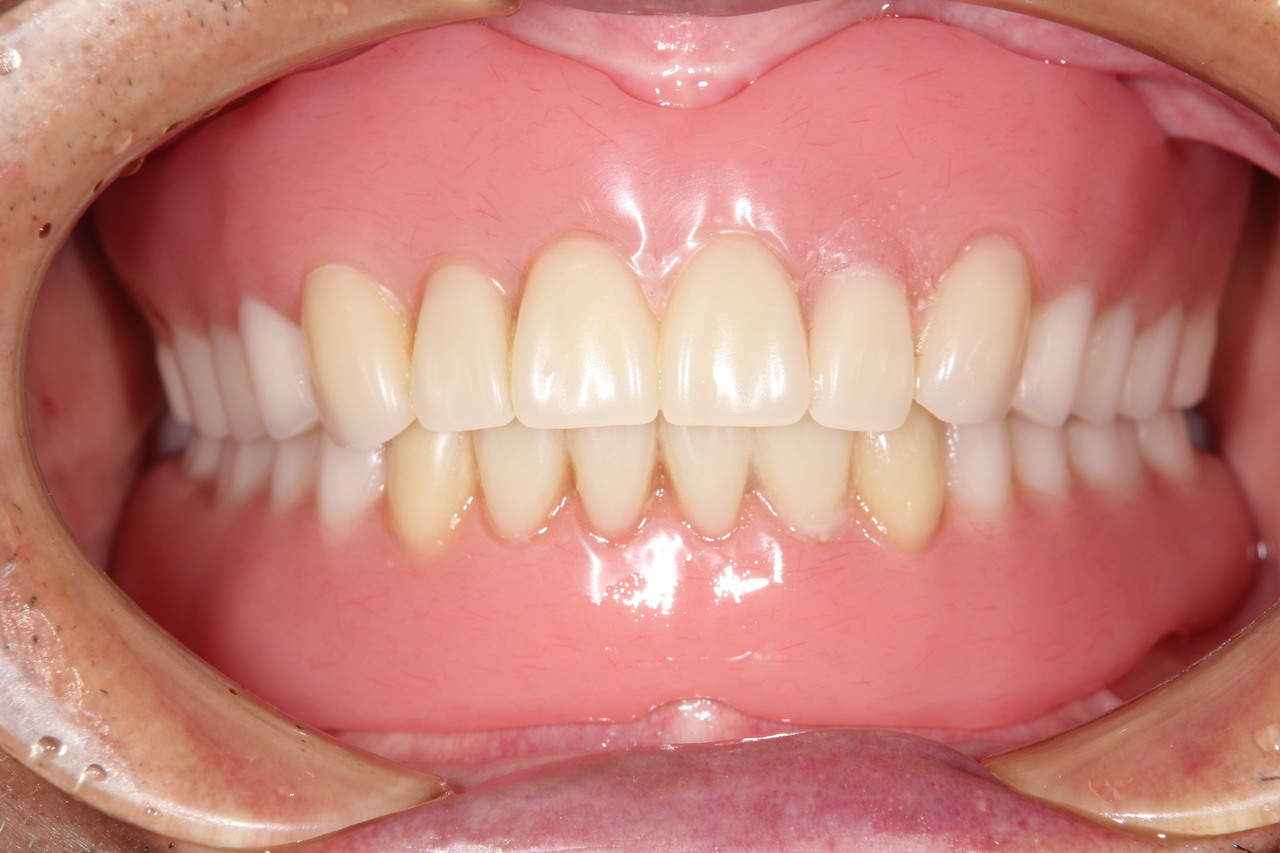

歯周病とインプラント(抜歯即時荷重)<ガイドシステムを使用した埋入法>

インプラント8本で14本の歯を並べたケース・仮歯代含む (函南町在住 女性

抜歯後、片顎8本のインプラントを埋入し、即日に仮歯を製作する事により、1日で片顎14本の歯を回復します。事前にインプラントを埋入する位置をCTによりシミュレーションし、埋入ガイド、仮歯を準備したうえで手術を行います。埋入ガイドにより、正確な位置にインプラントを埋入することができます。

最終的な被せ物装着

インプラントがしっかり骨に定着したら、型取りをして、最終的な被せ物を製作し、装着します。

完成後のレントゲン写真

最終的な被せ物を装着した状態のレントゲン写真。

(今回は下顎ですが、その前に上顎は治療済みです。)